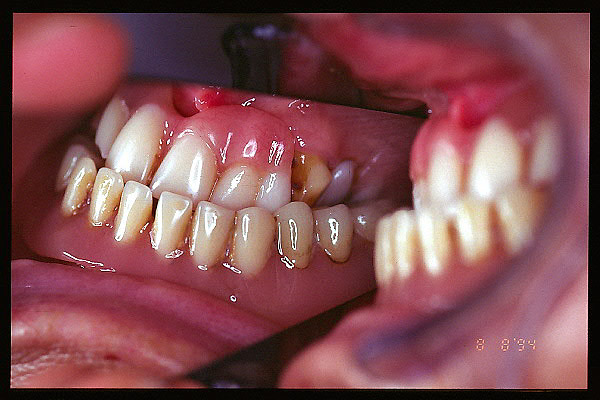

CM Caries y enfermedad periodontal avanzada